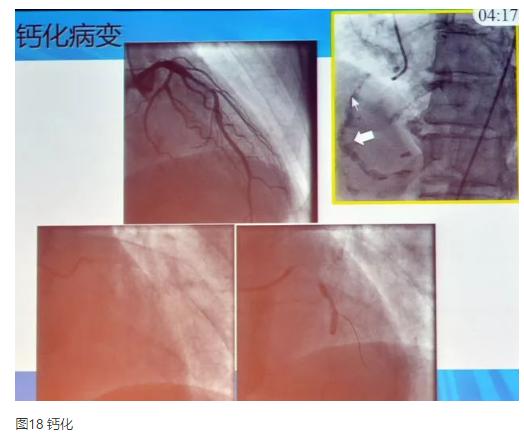

2.钙化病变

可分为显性钙化和隐性钙化。对于隐性钙化病变,需进行充分预扩张。